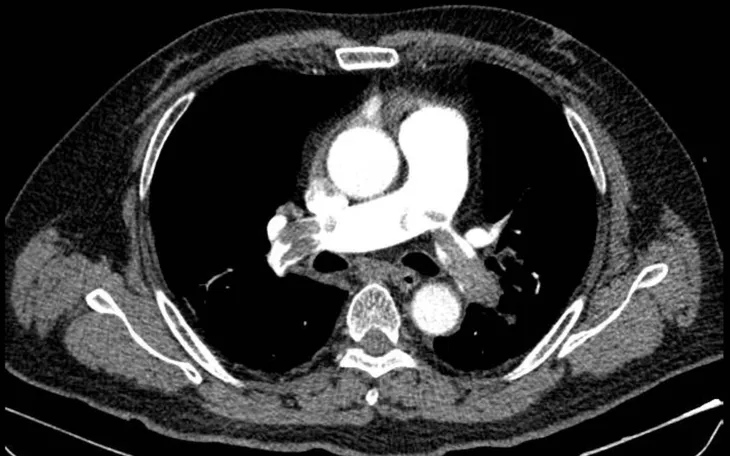

Hình ảnh chụp CT mạch máu phổi cho thấy huyết khối lớn bít tắc động mạch phổi hai bên. Ảnh: BVCC

Kết quả điện tim và siêu âm tim cho thấy dấu hiệu quá tải thất phải cấp, điển hình của thuyên tắc phổi nặng. Bệnh nhân được dùng thuốc vận mạch ổn định huyết áp, sau đó chụp CT mạch máu phổi phát hiện huyết khối lớn bít tắc động mạch phổi hai bên. Với sự phối hợp của Khoa Hồi sức tích cực, người bệnh được chẩn đoán sốc tắc nghẽn do thuyên tắc phổi nguy cơ cao và được điều trị bằng thuốc tiêu sợi huyết.